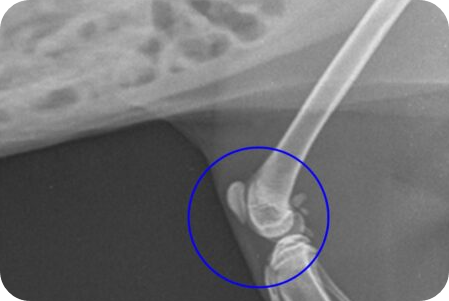

슬개골은 강아지 뒷다리 무릎 앞쪽에 위치한 작은 뼈로, 무릎 관절을 보호하는 역할을 합니다. 슬개골 탈구란 이 뼈가 정상 위치에서 벗어나 무릎 기능에 장애가 생기는 질환입니다. 주로 소형견, 특히 푸들, 말티즈, 치와와 등에서 자주 발생합니다.

슬개골 탈구는 진행 정도에 따라 1~4기로 구분됩니다.

- 1기: 평소엔 정상이나 손으로 밀면 슬개골이 쉽게 빠짐. 증상 거의 없음.

- 2기: 슬개골이 자주 빠졌다가 제자리로 돌아옴. 가끔 다리를 들거나 절뚝거림, 통증이 있을 수 있음.

- 3기: 슬개골이 항상 탈구되어 있으나 손으로 돌리면 돌아옴. 걸음걸이 이상, 근육 위축 발생.

- 4기: 슬개골이 항상 탈구되어 있고 손으로도 제자리 복귀 불가. 통증 심하고 정상 보행 불가, 다리 변형 동반.